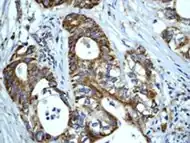

Human Hsp60, the product of the HSPD1 gene, is a Group I mitochondrial chaperonin, phylogenetically related to bacterial GroEL. Recently, the presence of Hsp60 outside the mitochondria and outside the cell, e.g. in circulating blood, has been reported [1], [2]. Although it is assumed that Hsp60 extra-mitochondrial molecule is identical to the mitochondrial one, this has not yet been fully elucidated. Despite the increasing amount of experimental evidences showing Hsp60 outside the cell, it is not yet clear how general this process is and what are the mechanisms responsible for Hsp60 translocation outside the cell. Neither of these questions has been definitively answered, whereas there is some information regarding extracellular Hsp70. This chaperone was also classically regarded as an intracellular protein like Hsp60, but in the last few years considerable evidences showed its pericellular and extracellular residence

HSP60 has been shown to influence apoptosis in tumor cells which seems to be associated with a change in expression levels. There is some inconsistency in that some research shows a positive expression while other research shows a negative expression, and it seems to depend on the type of cancer. There are different hypotheses to explain the effects of positive versus negative expression. Positive expression seems to inhibit “apoptotic and necrotic cell death” while negative expression is thought to play a part “in activation of apoptosis”.[23][24]

As well as influencing apoptosis, HSP60 changes in expression level have been shown to be “useful new biomarkers for diagnostic and prognostic purposes.” [23] According to Lebret et al., a loss of HSP60 expression “indicates a poor prognosis and the risk of developing tumor infiltration” specifically with bladder carcinomas, but that does not necessarily hold true for other types of cancers.[25] For example, ovarian tumors research has shown that over expression is correlated with a better prognosis while a decreased expression is correlated with an aggressive tumor.[25] All this research indicates that it may be possible for HSP60 expression to be used in predicting survival for certain types of cancer and therefore may be able to identify patients who could benefit from certain treatments.[24]